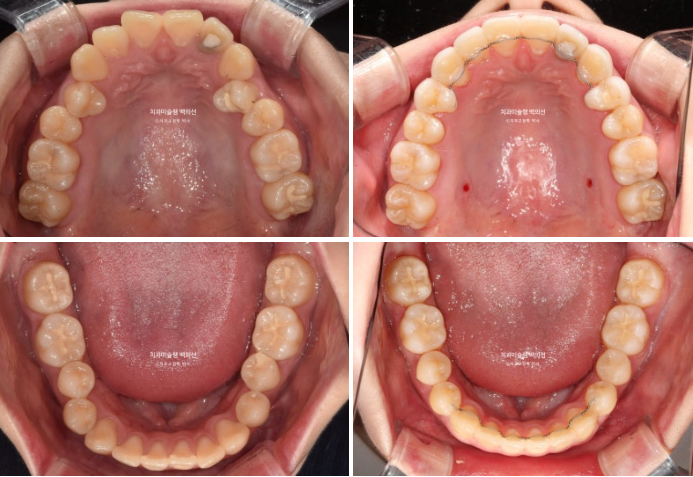

23.12~25.08

반대교합의 개선이 됩니다.

거미스마일과 잇몸돌출의 개선이 눈에 띕니다.

호두주름은 사라졌고 입이 편하게 다물리며 턱선이 예뻐졌습니다.

위 앞니 기준 약 2mm 합입이 되었습니다.

위 어금니도 마찬가지로 약 2mm 합입이 되었습니다.

한마디로 상악 전체치열이 2mm 합입되었고 뒤로는 약 2mm 후방이동 하였습니다.

앞니뿐 아니라 어금니까지 상악 14개 전체치열의 후방이동 및 합입으로 아래턱이 자가회전하며 턱끝이 짧아졌습니다.

무턱인 경우 상악 전체치열 함입교정은 치열뿐 아니라 얼굴 형태의 변화도 큰 교정입니다.

턱끝이 앞으로 나오니 일석이조입니다.